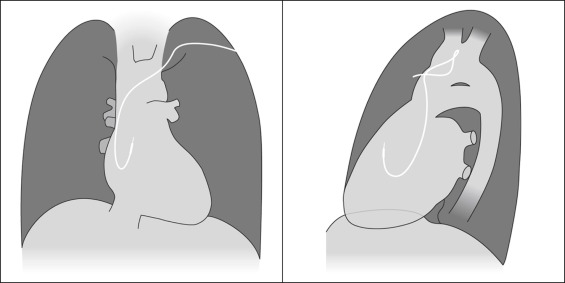

Endocardial Pacer Leads

The position and integrity of endocardial pacer leads should be verified, especially when pacemaker dysfunction is clinically suspected ( Graphics 23-1 to 23-4 ; Figs. 23-1 to 23-15 ).The most common cause of pacemaker dysfunction that is apparent on the chest radiography is distal lead displacement/misplacement.

With a right atrial lead , the tip should be in the right atrial appendage.

With a right ventricular lead , the tip should lie anteriorly at the apex of the heart.